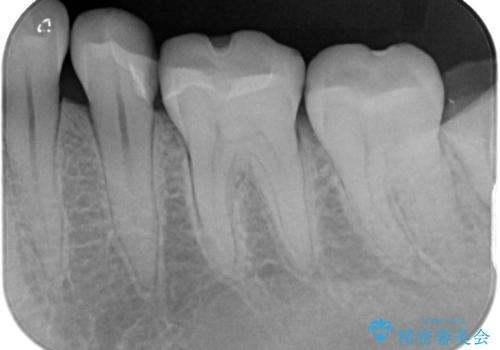

メタル修復物の場合X線を通さない性質があり、レントゲン写真を撮るとメタルの部分が真っ白に写ってしまうため、詰め物の下の虫歯が分かりにくくなってしまうというデメリットがあります。これに対し、今回の即日セラミック修復に使用したMarkⅡという材料は、レントゲン写真からもわかる通り歯の一番外側の部分(エナメル質)と同程度のX線透過性を持ちます。そのため装着後も定期的なメンテナンスにより虫歯の再発を早期に発見できるメリットがあります。